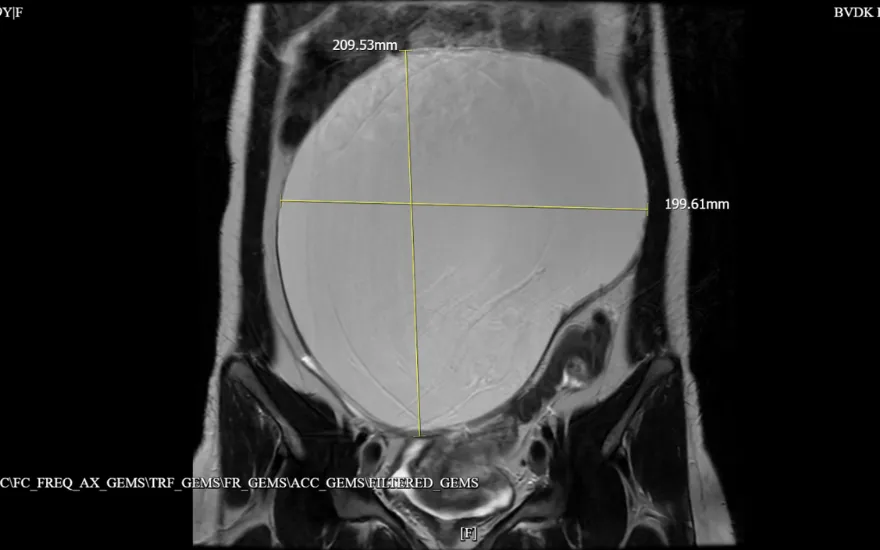

Kết quả siêu âm và chụp cộng hưởng từ (MRI) cho thấy người bệnh có khối u nang buồng trứng kích thước 209x199mm, căng lớn, choán toàn bộ ổ bụng. "Đây là khối u nang buồng trứng có kích thước rất lớn so với thể trạng của người bệnh. U phát triển nhanh trong thời gian ngắn, làm căng giãn ổ bụng và chèn ép các cơ quan lân cận. Nếu không xử lý kịp thời, người bệnh có nguy cơ gặp các biến chứng nguy hiểm như vỡ u, xoắn u hoặc xuất huyết trong ổ bụng", ThS.BSCKII Nguyễn Văn Xuyên (Trưởng Đơn nguyên Phụ khoa và Tuyến vú) nhận định.

Khối u kích thước hơn 20cm choán toàn bộ ổ bụng